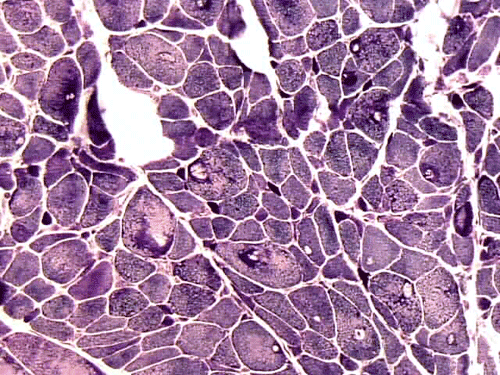

Physical examination revealed weight loss, weakness of arms, and stiffness of joints. He showed no cognitive deficiency and had normal cerebellar function. Muscles in the arm and hands were atrophic.  He had significant weakness of upper extremities and the muscle strength is 2/5 in deltoid, 3/5 in biceps and triceps, and 3/5 in brachioradialis, 3/5 in wrist flexion and extension. He had ulnar palsy in hands for over 10 years with the left side more affected than the right. Significant weakness in the muscle of the hands was also noted. There was no pain in the shoulders on palpation.  Muscle strength in lower extremities was 5/5 in all muscles except for 4/5 in iliopsoas.  The patient could squat up and down without much difficulty.  Sensory functions were intact in proprioception and light touch. There was bilateral decrease in  pinprick below the knees.  Reflexes were trace in upper extremities and were 2/4 knee jerk  and 1/4 ankle jerk.  There were no pathologic reflexes.  The functions of cranial nerve II to XII were intact.  There was good, function in the sternocleidomastoid muscles, but atrophic latissimus dorsi, trapezius, infraspinatus and supraspinatus muscle.  He had percussion tenderness of his bilateral ulnar cubital tunnels and right median tunnel.  Cervical and lumbar spines had full range of movement and were nontender.  CT scan of C-spine showed spondylosis in C3-7.  Head CT showed mild brain atrophy.  Electromyogram and nerve conduction studies of upper extremities were reported as suggestive of motor axonopathy.  Laboratory studies demonstrated slight elebation of rheumatoid factor to16.3, the sedimentation rate was 13, creatine kinase in serum was  171, and Lyme’s test was negative.  A muscle biopsy was perform as part of his workup. Representative photos from the muscle biopsy are shown below:

All stains and histochemistries are performed on frozen materials.

On hematoxylin-eosin stained sections, there is an increased variation of fiber diameter with many atrophic fibers intermingled with fibers of normal caliber. There is no evidence of fiber grouping or perifascicular atrophy. No inflammatory cells are present. There is also mild interstitial fibrosis (Panel A). On higher magnification, many fibers have a round concentric structure (Panel B). Irregular, centrally located depositions are also identified on modified Gomori's trichrome. The concentric nature, however, is not as obvious as in the hematoxin-eosin stained sections (Panel C). Type I and II fibers are not clearly separated in the ATPase preparation at pH 9.4. This is a common situation in chronically ill muscle (Panel D). The type I fibers are unusually dark. There is an increase in the proportion of type I fibers. The atrophic fibers are usually type II fibers. The concentric lesions are found predominantly in type I fibers (Panel E). There is an increase in PAS staining which is consistent with increased glycogen storage (Panel F). No increase in lipid content is demonstrated by oil red O (Panel G). On NADH-TR reaction, the concentric structures appear to have a clear central core that is devoid of enzymatic activity, a rim with intense enzymatic activity and a surround zone with relatively normal reactivity. These features are classic for target fibers (Panel H and I). No deficiency of laminin-2 (merosin) (Panel J) or dystrophin (Panel K) is demonstrated by immunohistochemistry. The central lesions are also immunoreactive for both laminin-2 and dystrophin. Immunohistochemistry for desmin demonstrate a core of strong immunoreactivity and also strong reaction in the sarcoplasmic membrane (Panel L and M). The target structures are also well demonstrated on semithin sections (Panel N). On electron microscopy, z-disc streaming is a common finding and they are often admixed with a substantial amount of dense granular electron dense substance (Panel O and P). There are also numerous cytoplasmic bodies characterized by radiating intermediate filaments (spheroid bodies) (Panel Q and R).